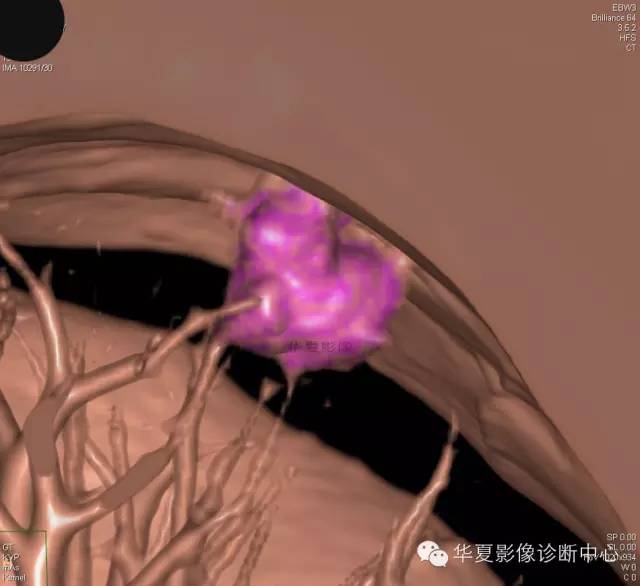

【病例学习】典型周围型肺癌CT病例一例

女,56岁,其父因肺癌去世,自觉胸部疼痛不适来诊要求拍胸片。

1.右肺上叶:肺组织1块,大小13×4×7cm。切面棕红色。2.右肺上叶肿物:灰白色组织一块,大小3×1×1.5cm。切面灰白色。3.右肺中叶结节:灰白色绿豆大组织1块。4.淋巴结:灰黑色绿豆大组织1块。

(右)肺中分化鳞状细胞癌。浸及胸膜。支气管残端切净。淋巴结未见癌转移(0/10)。